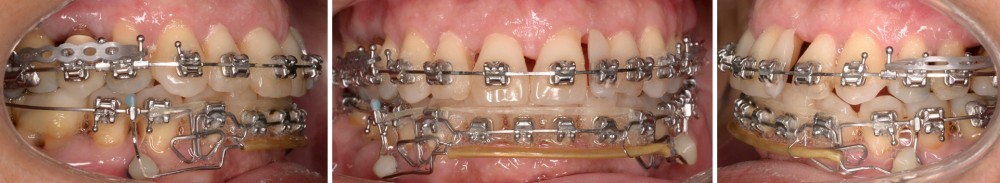

Le traitement d’orthodontie est réalisé en technique multi-attache vestibulaire (TGO, GC Corporation, Tokyo, Japon). La dent 46 n’est pas prise en charge dans l’appareillage, étant donné son faible ancrage et son pronostic réservé. L’alignement initial est effectué sur un arc Niti .016 au maxillaire et en trois segments à la mandibule (Niti .018x.025 en postérieur et Niti .016 de 33 à 43) (fig. 6).

En raison de l’ancrage dentaire postérieur mandibulaire très limité, il est décidé d’utiliser des ancrages osseux pour l’ingression du bloc incisivo-canin mandibulaire, afin de niveler l’arcade et de recréer le surplomb nécessaire à la fermeture des diastèmes maxillaires. Deux minivis d’ancrage sont positionnées entre les dents 32/33 et 42/43, après réalisation d’un examen CBCT localisé sur l’arcade mandibulaire (fig. 7 et 8). Ces minivis antérieures ont été rapidement déposées, en raison de leur mobilité et de la gêne importante de la patiente liée au positionnement très apical du fait de l’alvéolyse.

Des minivis d’ancrage sont alors positionnées entre les dents 34/35 et 44/45 (fig. 9). Un sectionnel d’ingression antérieur (acier .018x.025) est fixé sur celles-ci, tout en passant par des tubes en croix situés entre les prémolaires afin d’éviter le dévissage des minivis. L’ingression est réalisée via des ligatures reliant l’arc orthodontique principal (TMA .018x.025 avec boucles double-delta) au sectionnel, selon une direction permettant l’ingression tout en limitant la composante de vestibulo-version. Du stripping mandibulaire a été réalisé de mésial de 33 à mésial de 43 afin de corriger l’indice de Bolton.

Une fois le surplomb augmenté, la fermeture maxillaire a été réalisée par une technique de glissement sur un arc acier .020x.025 à bouts arrondis.